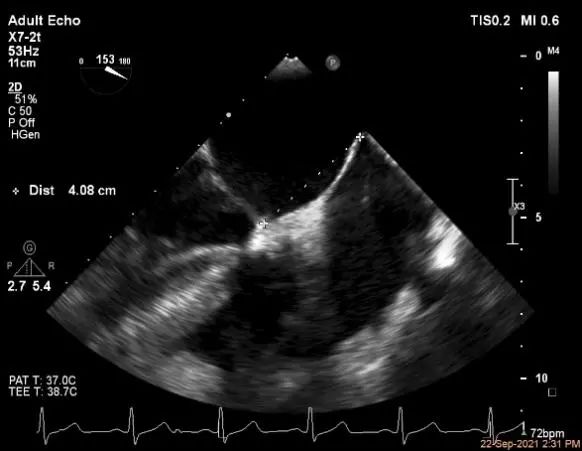

穿刺高度:4.08cm

穿刺高度:4.3cm